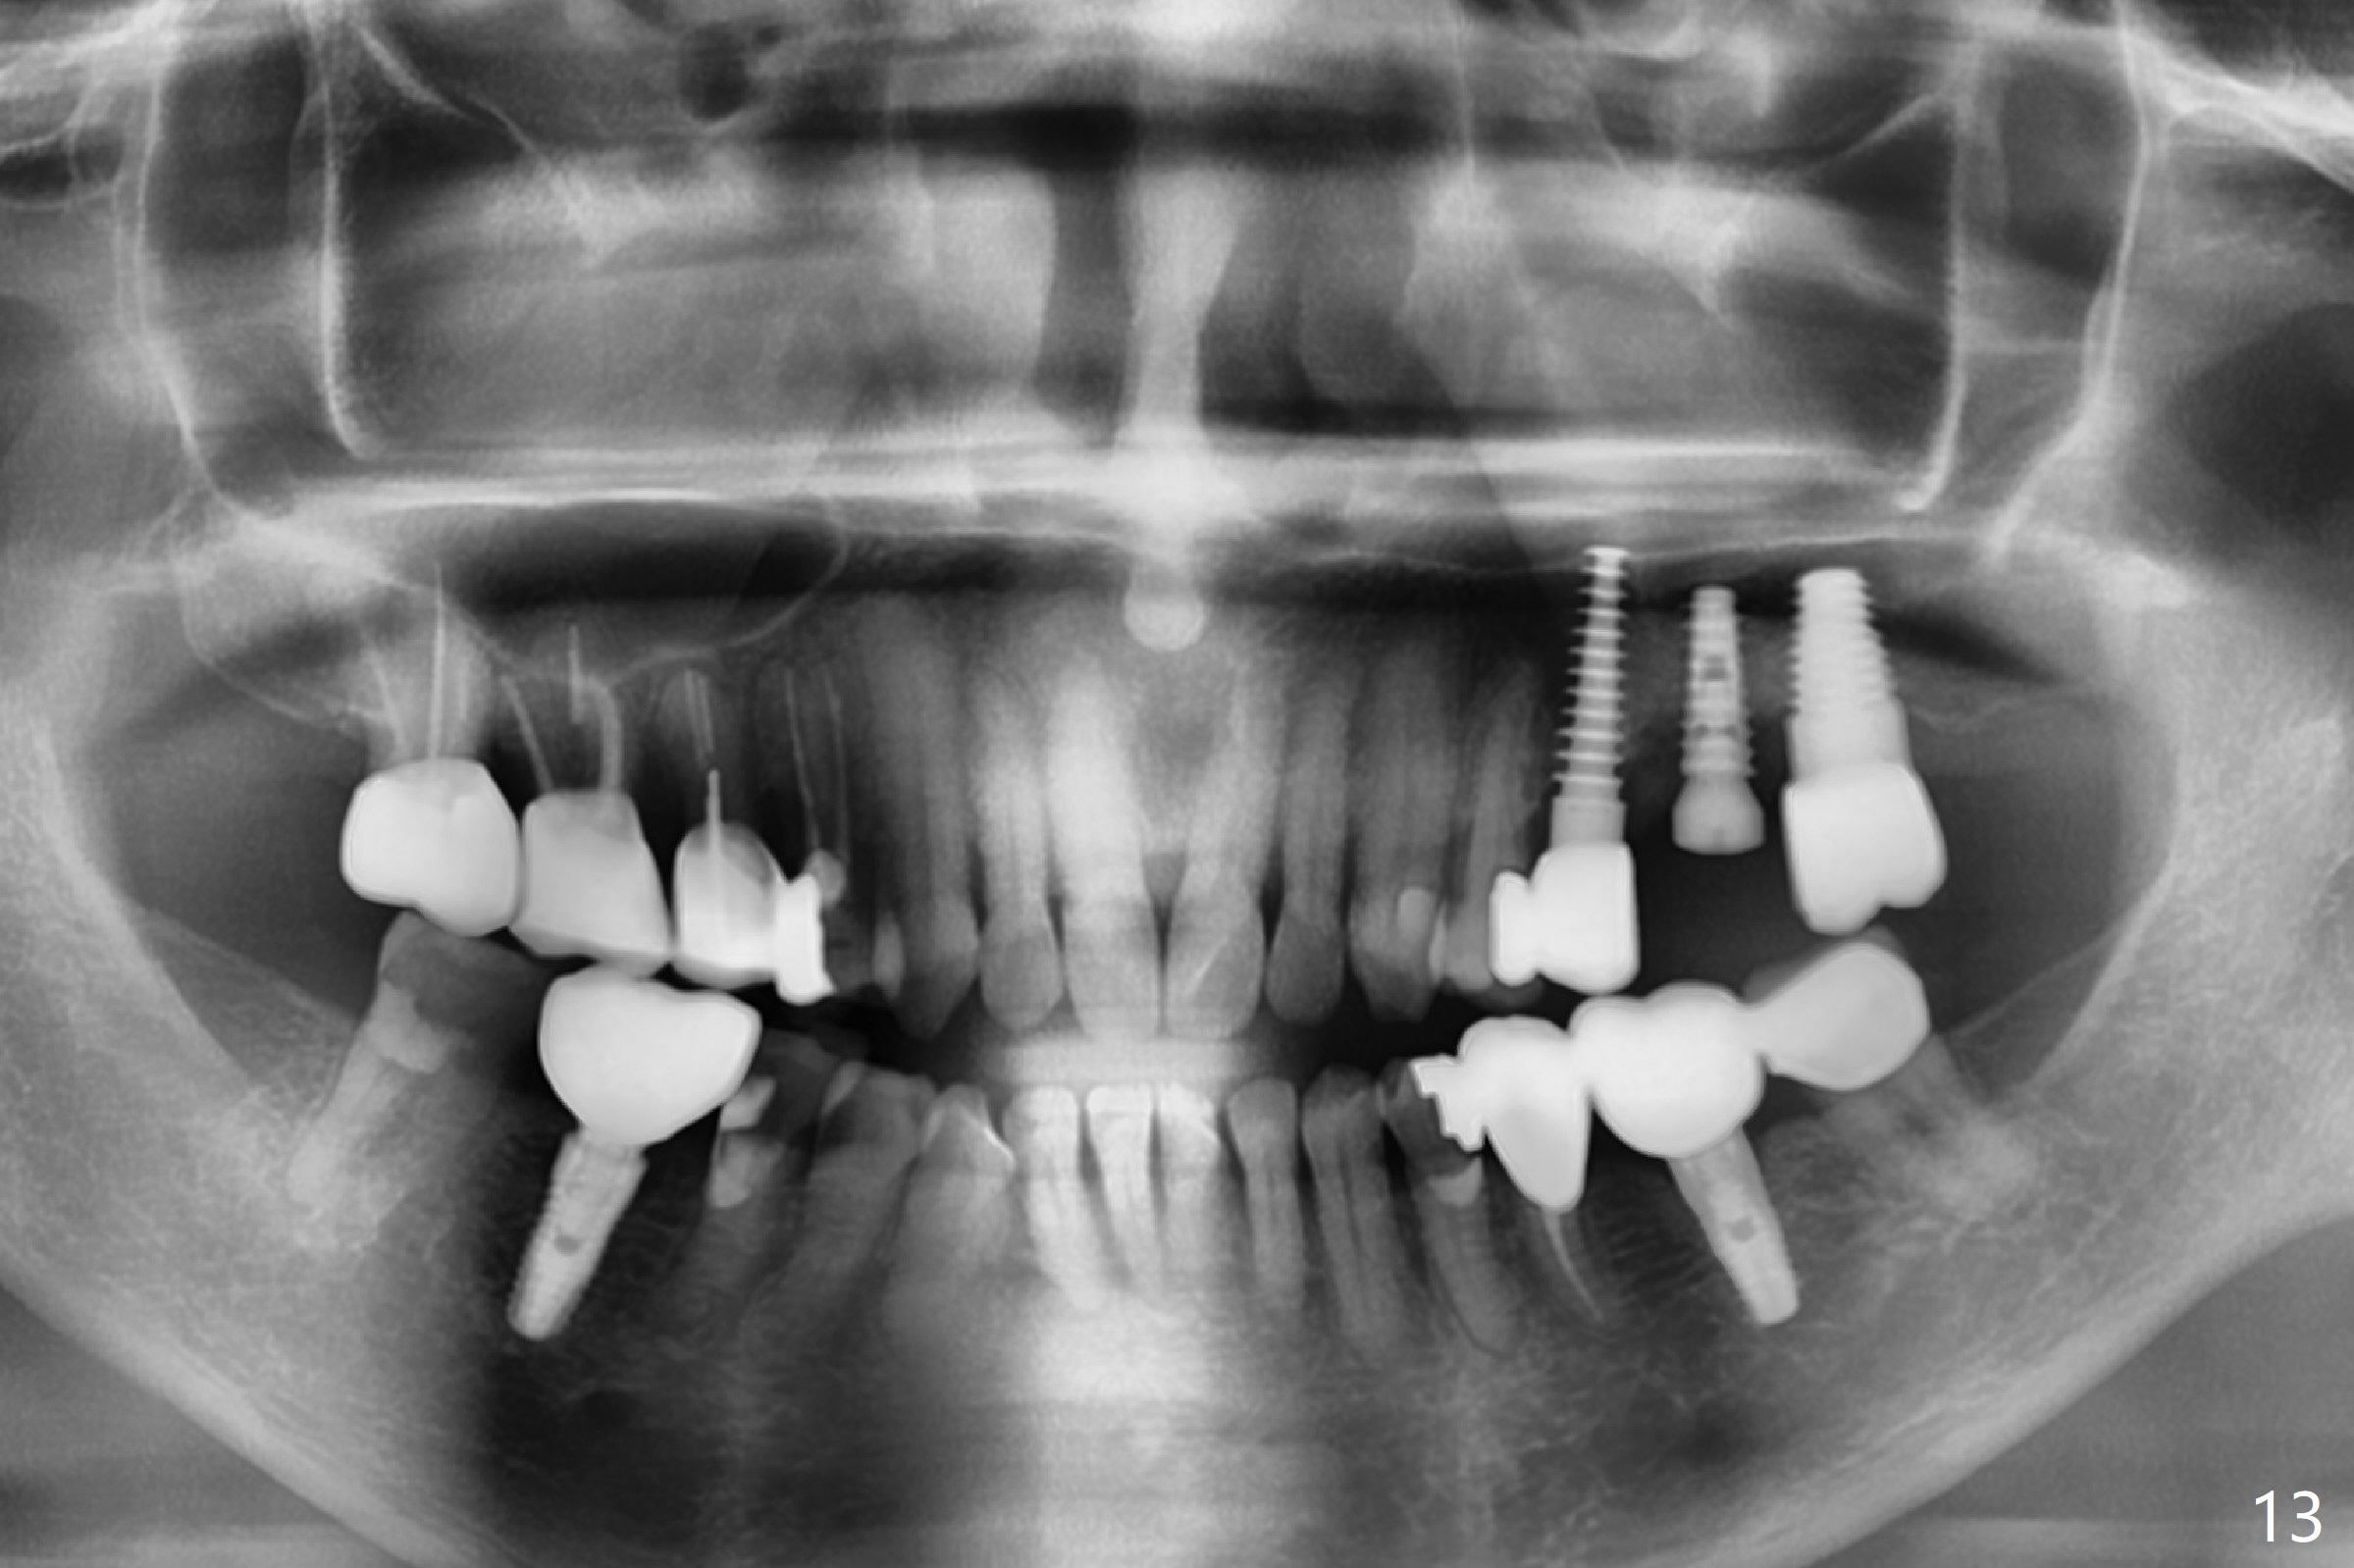

Initial osteotomy in the septum of the tooth #14 is 9 mm, approximately 2 mm from the sinus floor (Fig.1).  Subsequent osteotomy depth is 11 mm, followed by insertion of a 4.5x11 mm dummy implant (Fig.2).  After use of Magic Drill (MD) 4.8 mm for 9 mm, a 5x11 mm IBS implant is placed with sinus lift without additional bone graft (Fig.3 *).  In contrast, autogenous bone (from MD) and Vanilla Graft are meticulously placed in the remaining socket (+) before and after placement of a 6.5x5.7(2) mm abutment.  An immediate provisional is fabricated to close the sockets.  There is buccal tenderness 1-3 months postop.  There is distopalatal implant thread exposure.  A healing abutment (5.5x2 mm) is placed.  CT confirms thin buccal plate (Fig.4,5).  It appears that the implant should have been as palatal as possible.  The tenderness remains for the next 2 weeks.  When the healing abutment is removed, the implant seems to have been placed shallow, ~ 1 mm subgingival (Fig.6).  With local anesthesia, the implant is reversed to clean the coronal threads with Titanium brush and copious irrigation (Fig.7).  The implant is then placed ~4 mm subgingival (Fig.8) and slightly subcrestal (Fig.9,10).  It appears that the postop bone loss (Fig.9 *, as compared Fig.1,2) makes the implant look to be placed too shallow.  When the implant is being placed deeper, the buccal plate feels intact.  The early periimplantitis is apparently due to postop bone loss more than buccal placement, although certain degree of buccal bone resorption must occur.  A 6x4 mm healing abutment is placed.  Left facial swelling develops 2 days post implant elevation (Fig.11,12, as compared to preop (Fig.13)).  The left maxillary sinus cloud (Fig.12) appears to be a false positive finding, since the same feature exists prior to implant elevation (Fig.13).  Both sinuses look clear prior to implant elevation (Fig.14).  Amoxicillin switches to Augmentin and Flagyl, since the patient is reluctant to have the implant removed.  Finally the sinus infection is under control.  The patient feels left facial swelling 9 months postop (5 months post elevation) and reports left nasal discharge ~ 1 month earlier.  There is mild buccal plate tenderness.  The implant seems to be buccally placed (Fig.15,16), although there is no significant change radiographically (Fig.17).  The implant is removed with bone graft (Fig.18 *).  To avoid complication and failure, an immediate implant at the upper 1st molar should be short and placed deep.